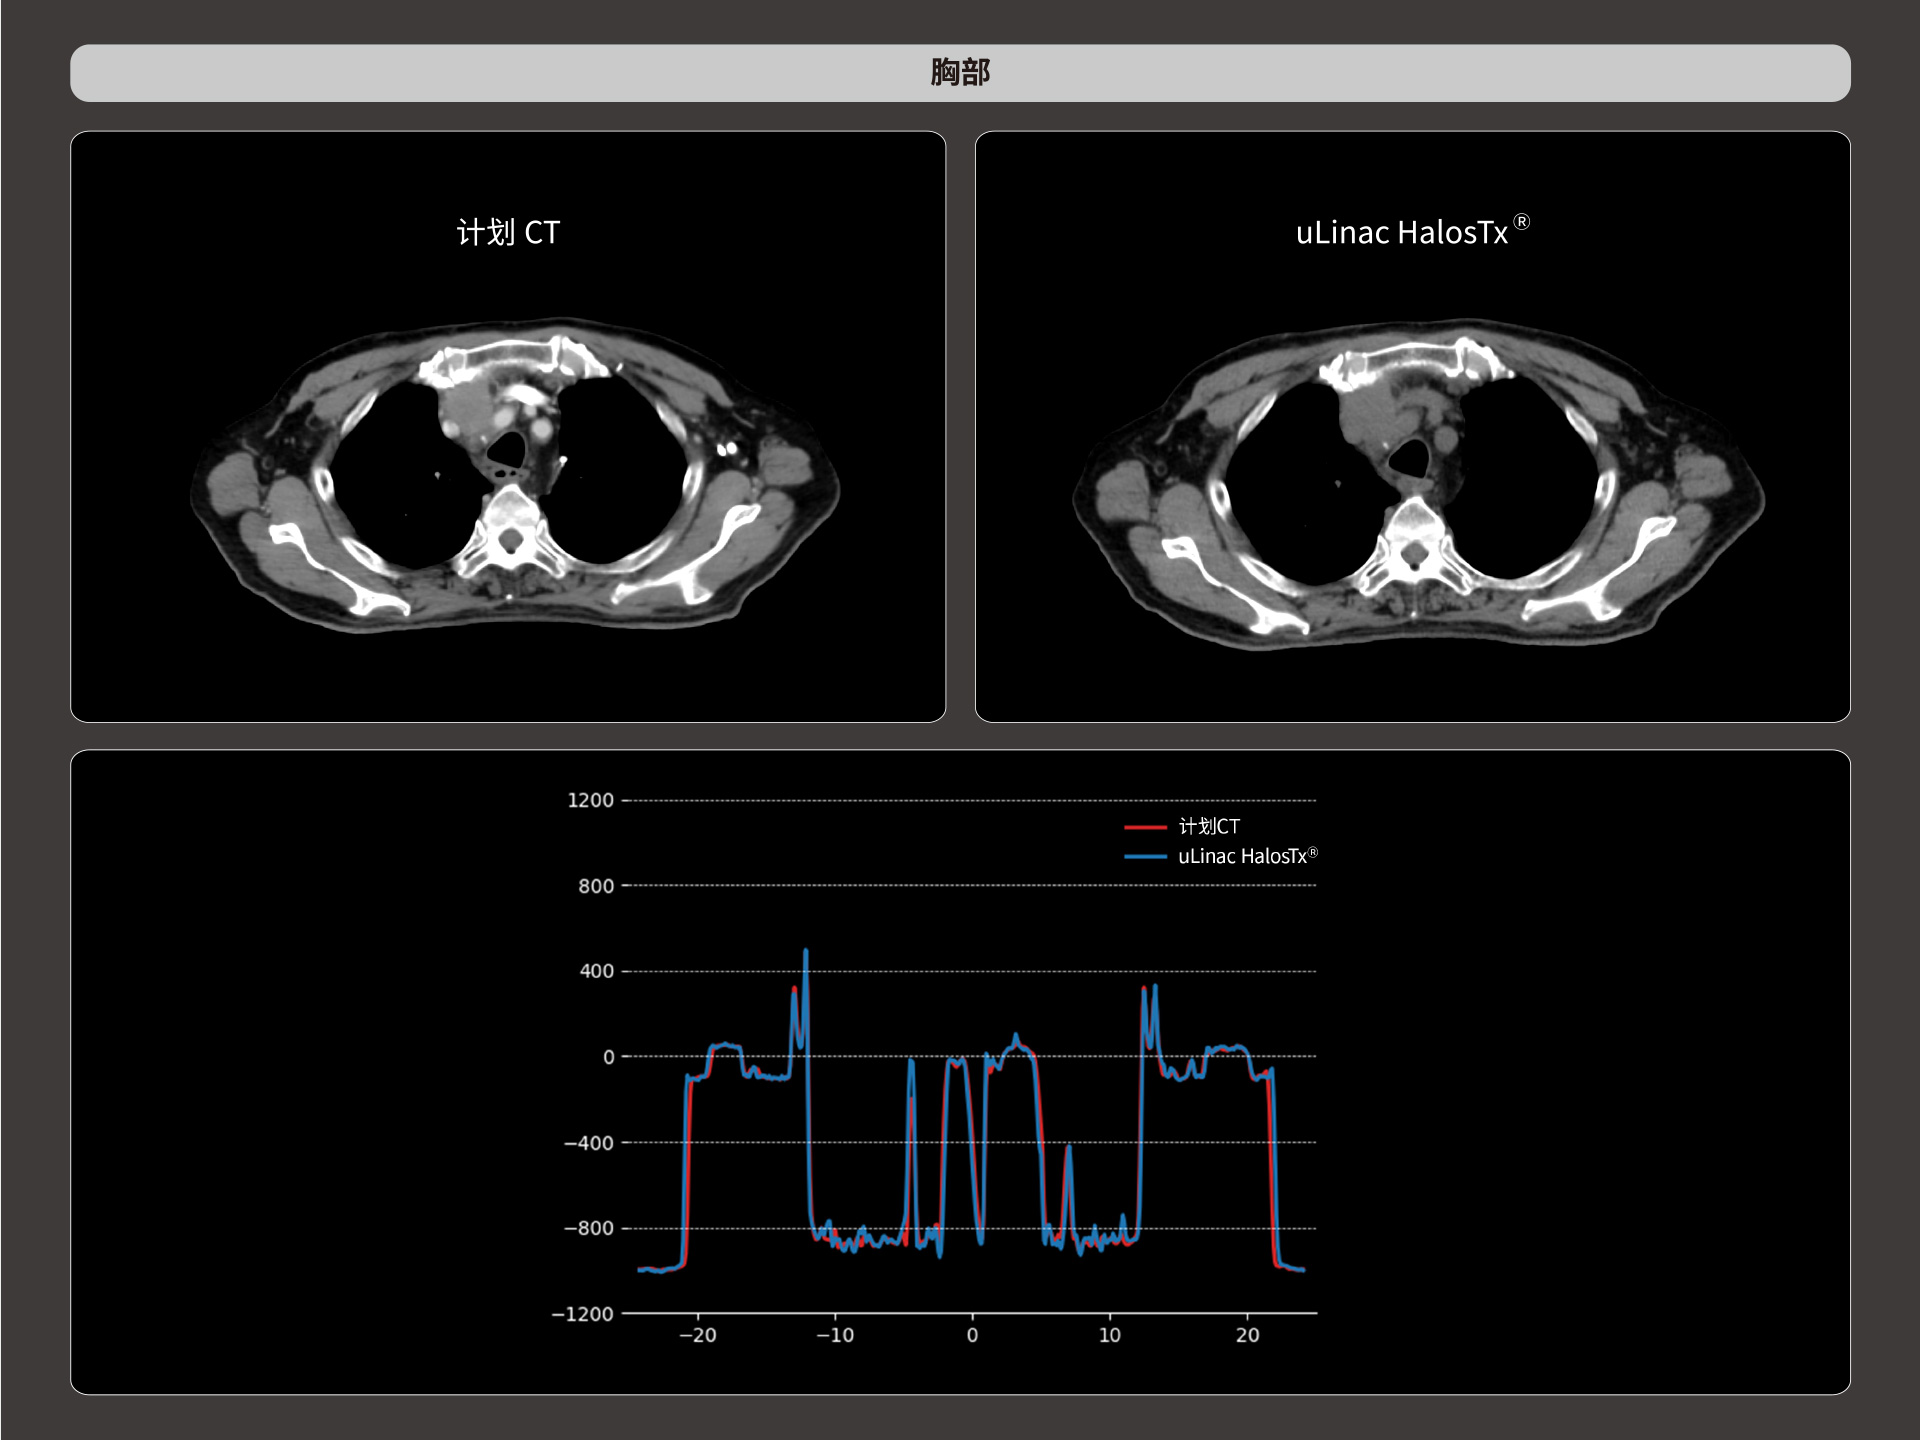

扇形束成像,极低散射,媲美CT-sim的影像品质

3mm @ 0.3% 高软组织对比度,0.55mm薄层扫描,精确鉴别肿瘤靶区边界

精准CT值,完美满足勾画、剂量计算要求

提供传统 的CT 模拟机所一致的HU值精度(±10HU)

HU金标准

从数据源头提升图像质量,高清呈现细微变化,全面精进机载影像实力